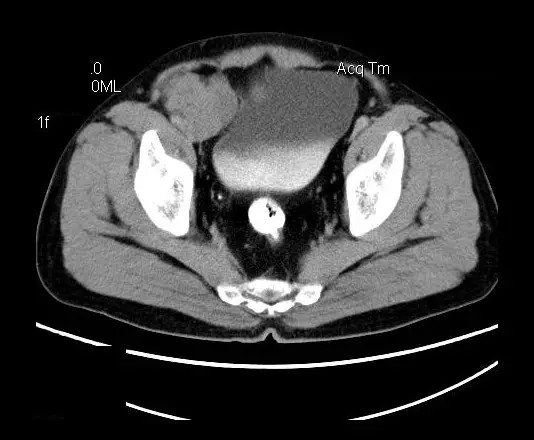

男,50岁,发现盆腔包块一月,无明显触痛,不伴发热。

【影像表现】

盆腔右前侧及邻近腹股沟区可见多发大小不等的聚集生长的结节影,病灶呈软组织密度,边缘尚规整,分界尚清,增强扫描可见不均匀强化。膀胱局部受压,盆腔未见明显肿大淋巴结影。

“盆腔”多发性神经鞘瘤